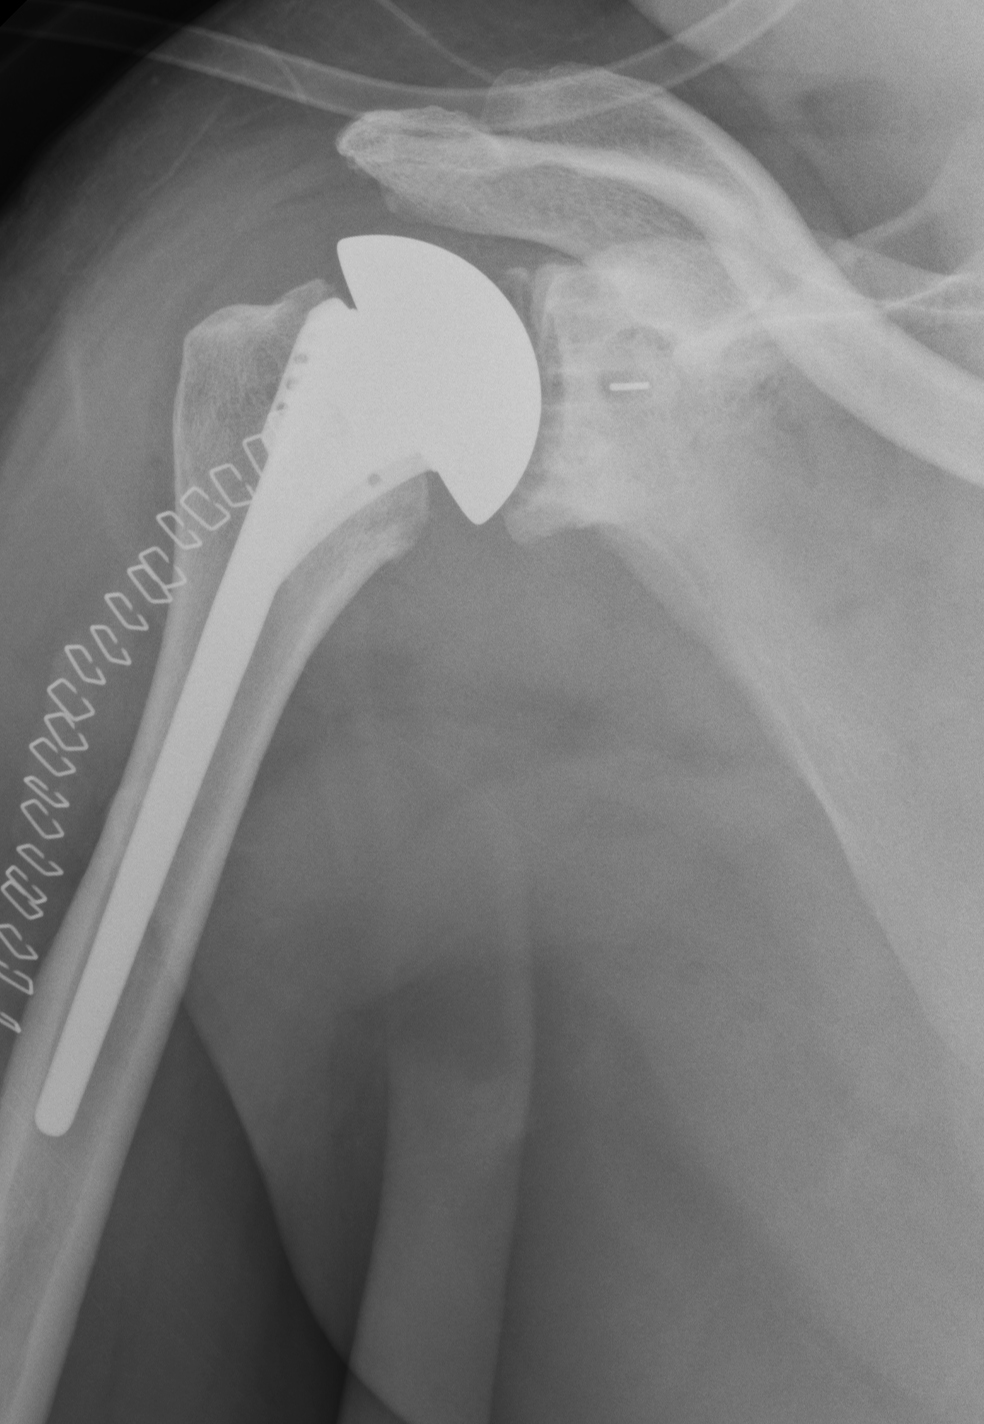

Post operative xray of a relatively large size rotator cuff tear with Rotator Cuff Surgery Failure failed rotator cuff repairs present a complex issue for treating surgeons. Rcr can be considered a multifactorial. treatment of patients with failed rotator cuff repair ranges widely, from conservative treatment to arthroplasty. rotator cuff repair (rcr) is a common procedure performed by orthopedic surgeons via arthroscopic, open, or mini. two authors (al and pjd) independently identified. Rotator Cuff Surgery Failure.

Patient Following Revision of Failed Rotator Cuff Surgery Failure treatment of patients with failed rotator cuff repair ranges widely, from conservative treatment to arthroplasty. rotator cuff repair (rcr) is a common procedure performed by orthopedic surgeons via arthroscopic, open, or mini. the most common causes of pain after rotator cuff surgery are (1) that the shoulder is still recovering from the surgery itself and (2) the. Rotator Cuff Surgery Failure.